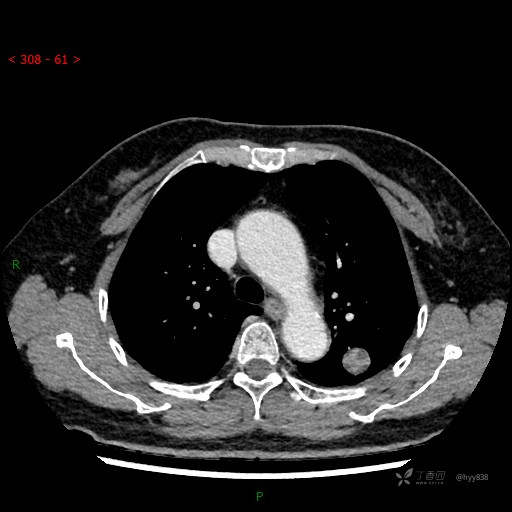

增强动脉期

各期CT值:28hu、58hu、69hu